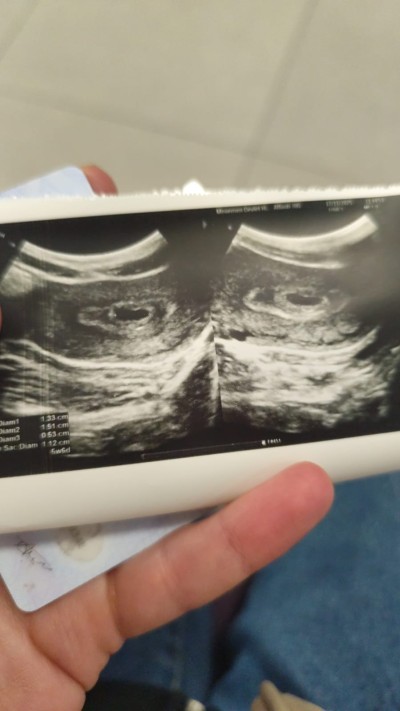

kizlar kese var Bebek yok 6+0 normalmi tekrar kontrole ne zaman gitmeliyim

Gebelik haftası 6

Çok normal bnmde 6+3 ken yoktu. İki hafta snra gel dedi 8 haftalıkken gttim gördüm çok şükür. Sende görürsün insallah

Normaldir bende 8 haftalık olduğunda gördüm bebeği

Normal canım benim geç döllenme var 8 haftalık yerine 6 haftalık görünüyor. 6+0da görülmedi bugün 6+5te hem bebek hemde kalp atışını duyduk çok şükür

Bnde suan ayni durumdayim 6 haftalikken gitim kese var bebek yok dendi 7 6da gitim bebegi gorduk ama kalp atisini duyamadik persembe gunu duyariz insallh onuda